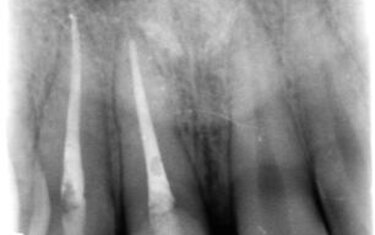

Figure 2: Patient delay in seeking treatment resulted in root canals on both teeth being needed due to irreversible pulpitis.

This case showcases how a trauma patient can be treated immediately in a single visit. This 19-year-old male presented to my practice with severely fractured teeth #7 and #8 (Figure 1) as a result of being assaulted. Unfortunately, he had waited 48 hours before seeking treatment and the exposed pulp required us to perform root canals on both anterior teeth with core buildups to retain the crowns (Figure 2).  The teeth were prepped and the preps scanned for import into CAD design software (ChairsideCAD, Exocad) (Figures 3 and 4). Two full-contour crowns in shade A2 (IPS e.max CAD, Ivoclar Vivadent) were milled, then crystalized, stained, glazed and placed in the mouth (Figure 5). One year later the patient returned for a post-op appointment to ensure the success of the root canal procedure and that the margins had filled in nicely with no inflammation (Figures 6 and 7).

Figures 6 and 7 (below): The patient one-year later confirmed marginal integrity of the two crowns and success of the root canal therapy.